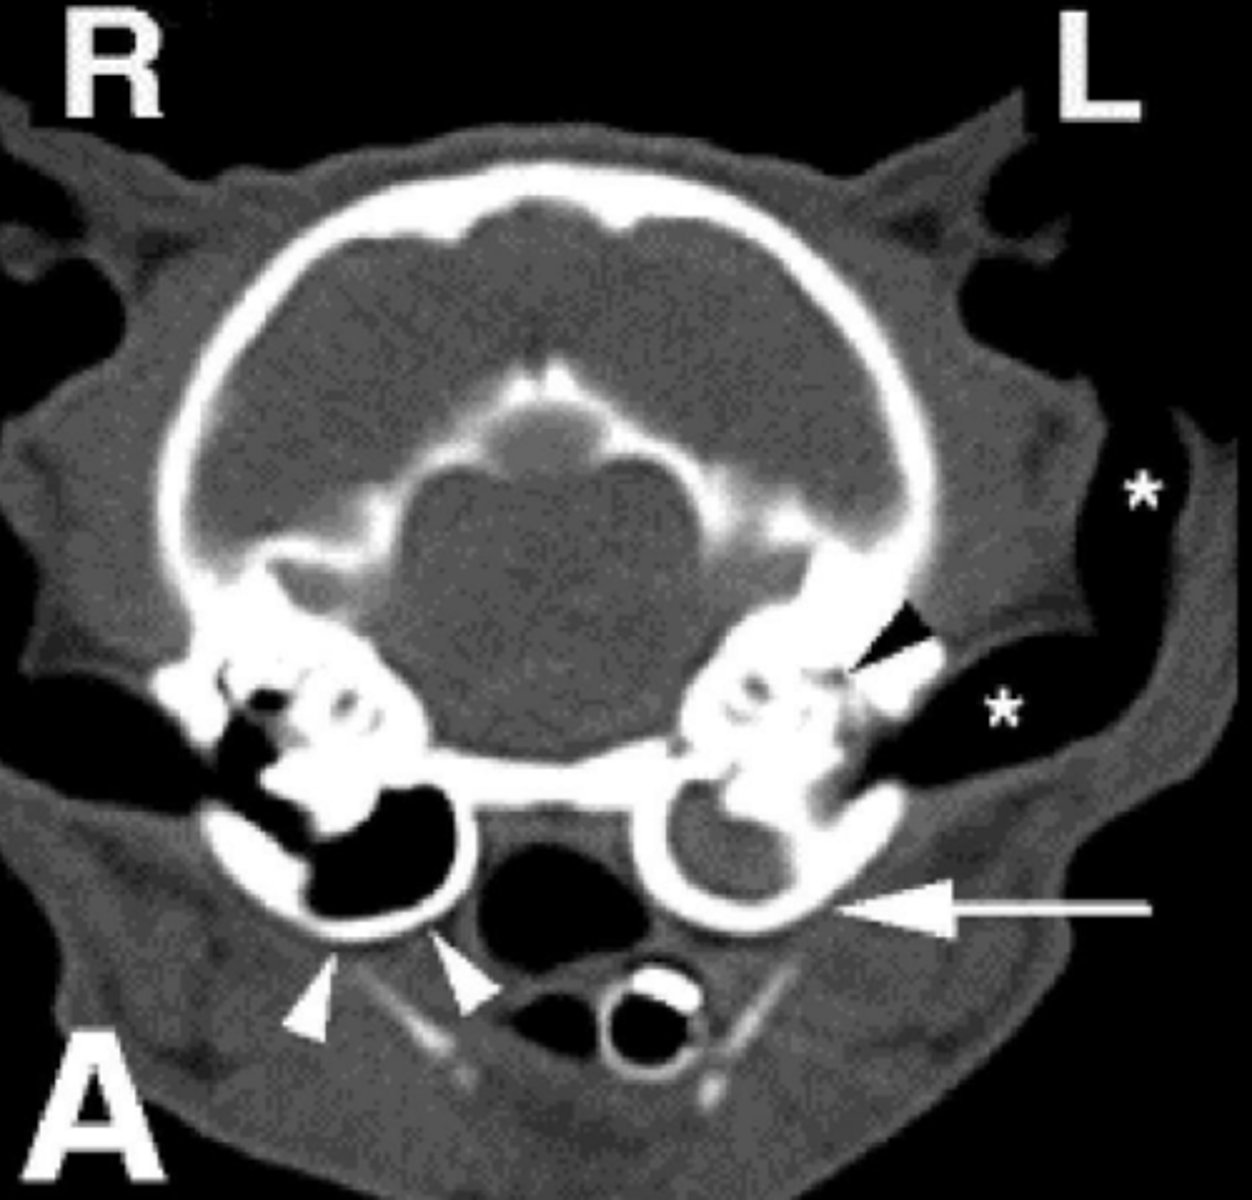

What are the top differential diagnoses for this image?

1. polyp

2. infection (otitis media)